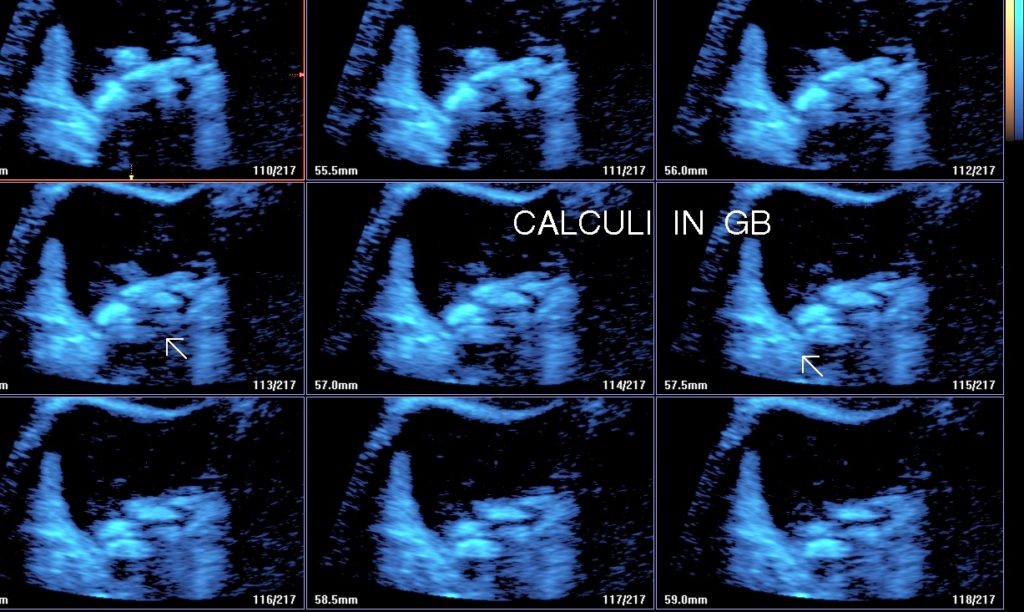

• Cholelithiasis: Presence of calculus/ calculi in gall bladder with normal wall thickness is known as cholelithiasis.

• Findings: Shows presence of calculi in gall bladder/ common bile duct, its mobility & complications.

• Multiple Calculi